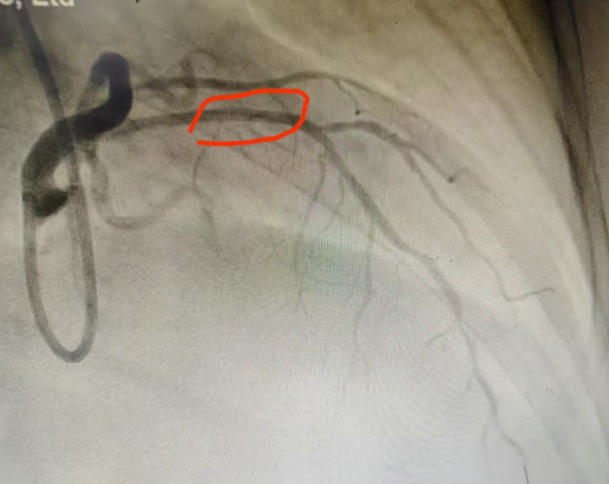

"若不打通堵塞的血管,心衰随时会复发。"心内二科马东亮主任判断患者心脏最重要的血管前降支存在严重狭窄。经与家属深入沟通,导管室团队为患者实施冠脉造影,结果证实前降支近段堵塞超过90%。通过微创介入药物球囊扩张成形术,团队成功开通病变血管,术后患者心脏功能得到根本改善。

术后